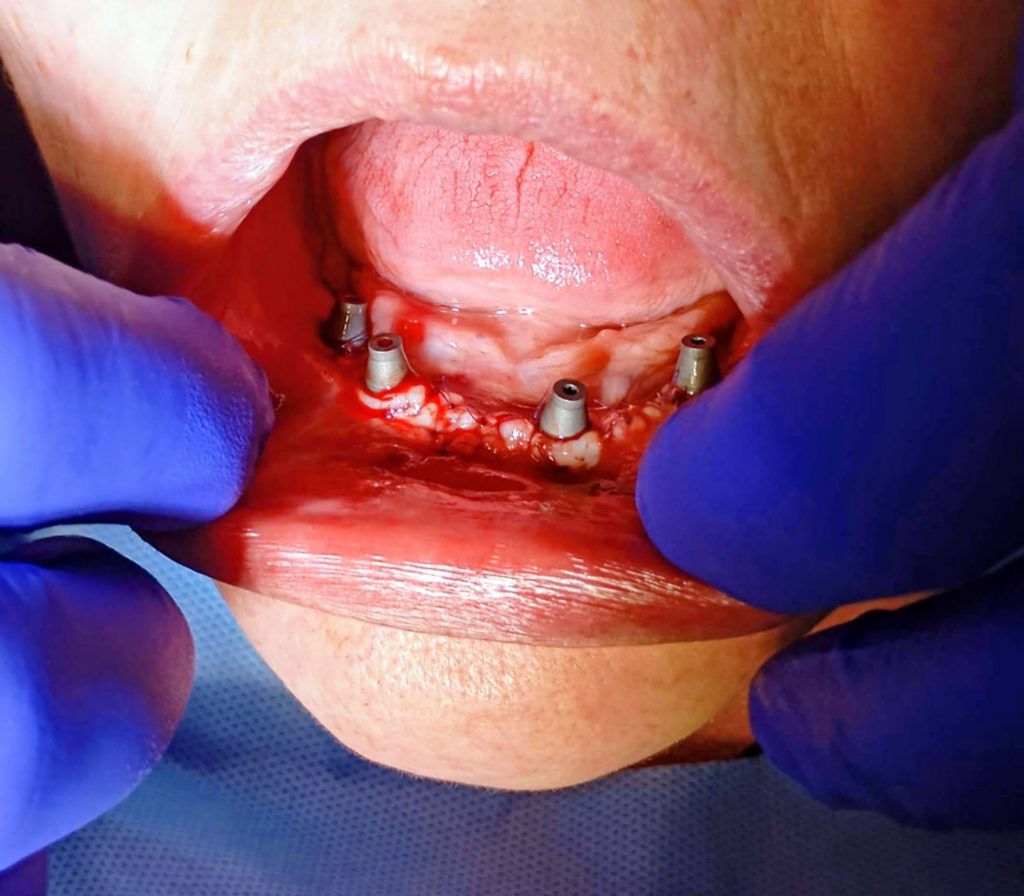

Inserarea Implanturilor și a Multiuniturilor: După poziționarea strategică a implanturilor, au fost montate bonturile de tip Multi-Unit, elementele care fac legătura între implant și viitoarea lucrare protetică.

Scanarea „One Shot”: Utilizând tehnologia Scan Abutment One Shot, echipa a realizat scanarea intraorală a arcadei. Această metodă scurtează timpul petrecut de pacient pe scaun și elimină erorile umane asociate cu amprentarea clasică cu silicon.